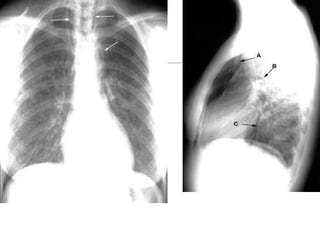

Radiographic Signs of Pneumomediastinum

Subcutaneous emphysema

Thymic sail sign

Pneumoprecardium

Ring around the artery sign

Tubular artery sign

Double bronchial wall sign

Continuous diaphragm sign

Extrapleural sign

Air in the pulmonary ligament

• 82.

Radiographic Signs ofPneumomediastinum Subcutaneous emphysema Thymic sail sign Pneumoprecardium Ring around the artery sign Tubular artery sign Double bronchial wall sign Continuous diaphragm sign Extrapleural sign Air in the pulmonary ligament